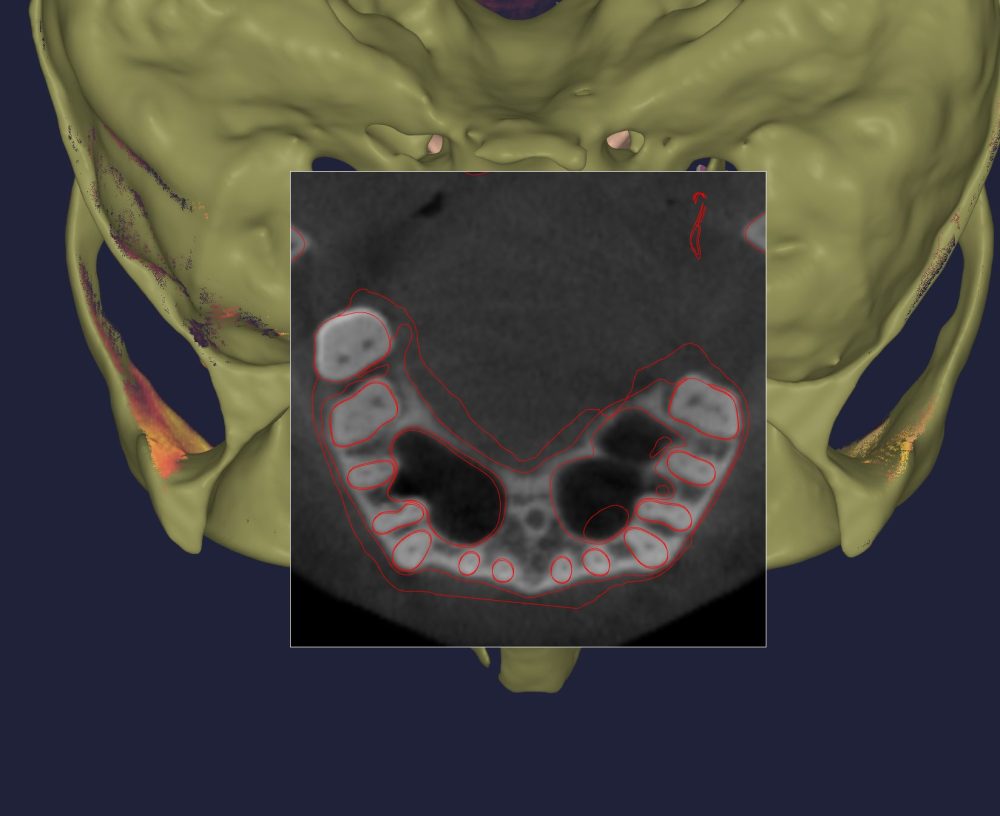

❹解剖学的な歯根と歯槽骨の形態

これは「道路(歯槽骨)と車(歯根)のサイズ」で説明すると分かりやすいと思います。細い道に大きな車を通すなら道幅を拡張する必要があります。若く高性能なタイヤ(歯根膜)があれば道路拡張も順調に行われますが、成人矯正では拡張工事は時間がかかるか途中でストップしてしまうのです。